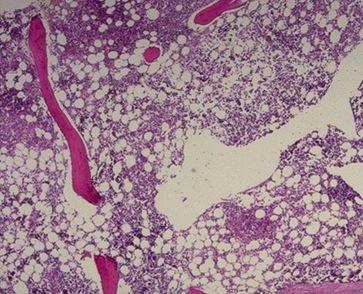

Osteopetrosis (stone-like bones) aka marble bone disease

X-rays: Bones lack medullary canal

Microscopic: Medullary cavity abnormally filled with primary spongiosa and no hematopoietic elements

Etiopath:

Sx:

C&C